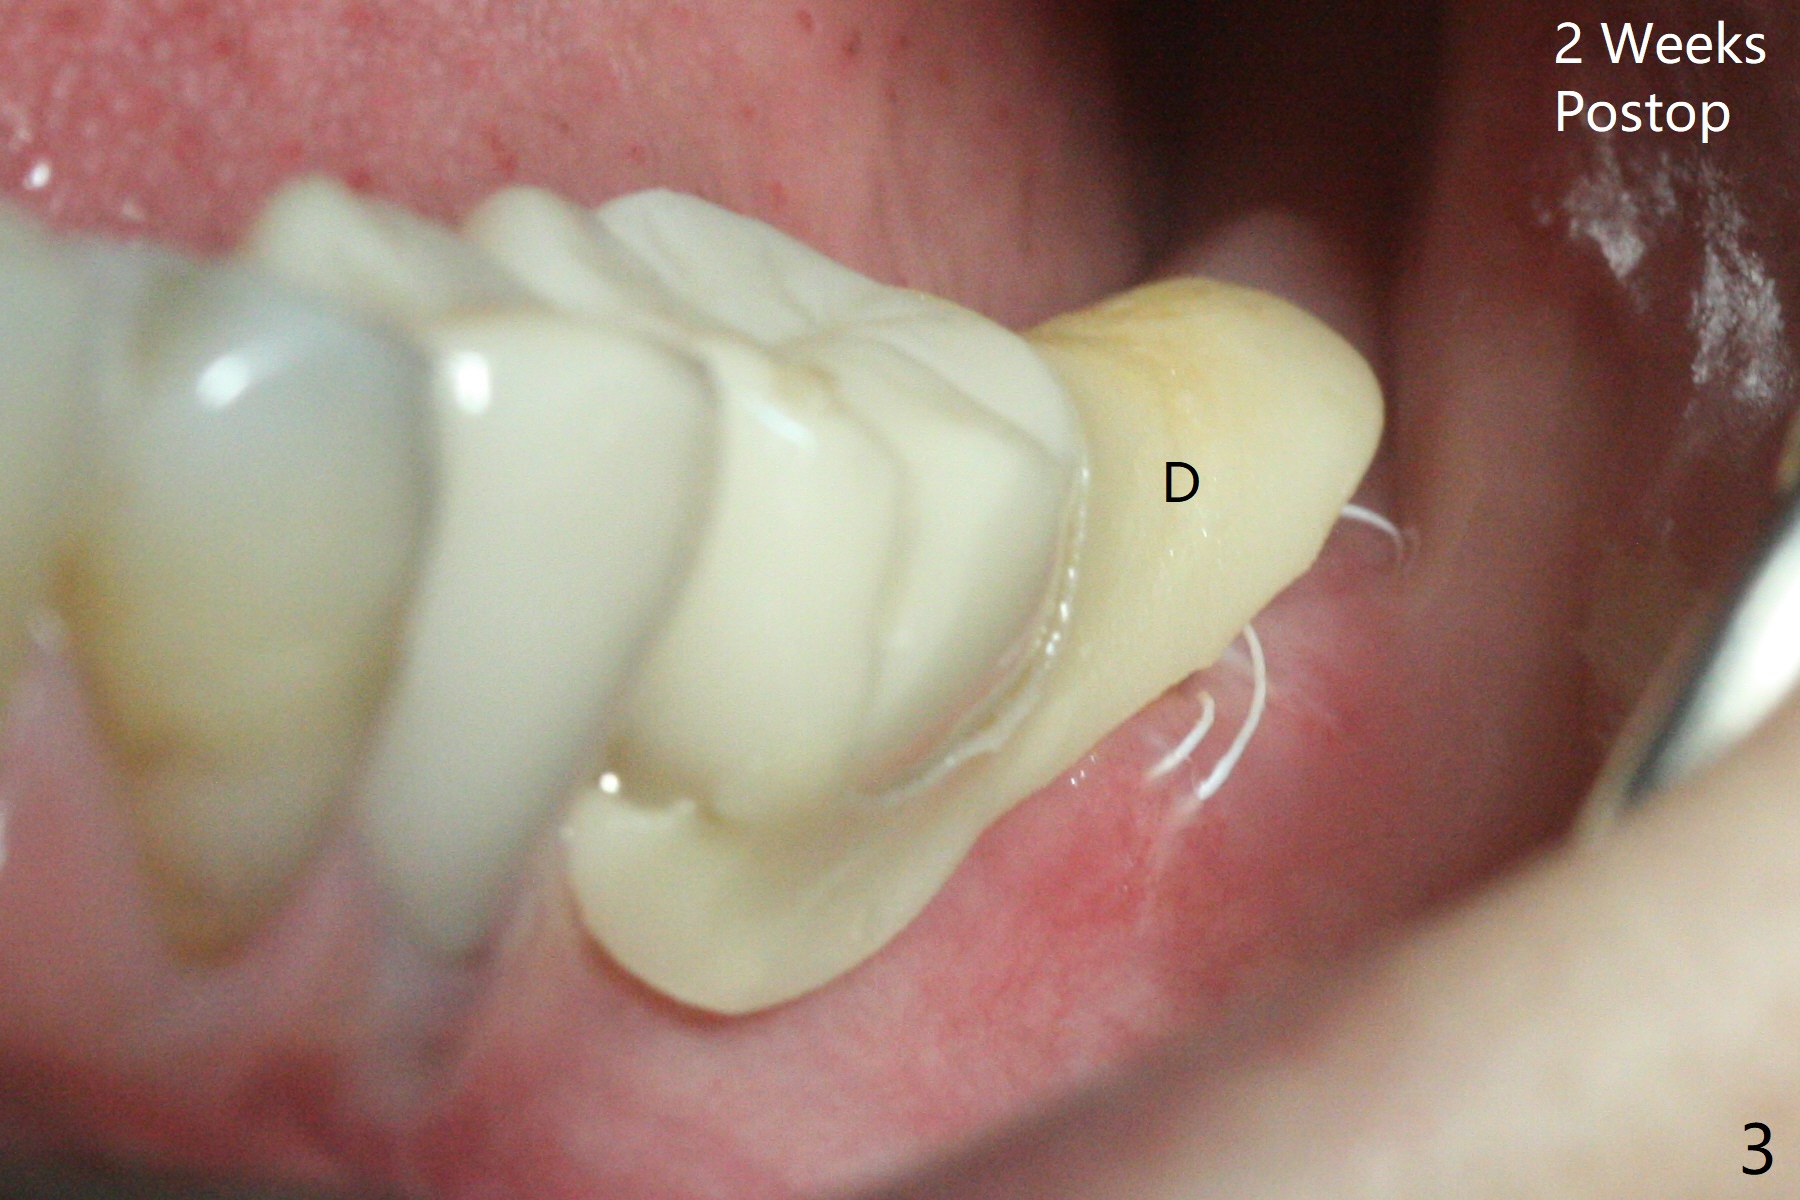

A 74-year-old woman is nervous with possible extraction and implant at #18 with subgingival caries (Fig.1 *), because 4 of immediate implants have been and possibly need to be redone. In contrast delayed implant at #19 fair the best with formation of the dense bone next to the coronal macrothreads (Fig.2 *) in spite of exposure of the microthreads (<). When the tooth #18 is extracted, the socket opening appears to be narrow. The lingual septum is narrow and short (possible C canal). Fine particles of cortical allograft mixed with blood is placed in the mesial (M) and distal (D) sockets and covered by compressed collagen plug and Cytoplast. PTFE suture is used. The future implant should be small in diameter and placed subcrestal. Acrylic dressing is in place and loose 2 weeks postop (Fig.3), presuming keeping Cytoplast in place. The dressing is going to be removed 5 weeks postop.